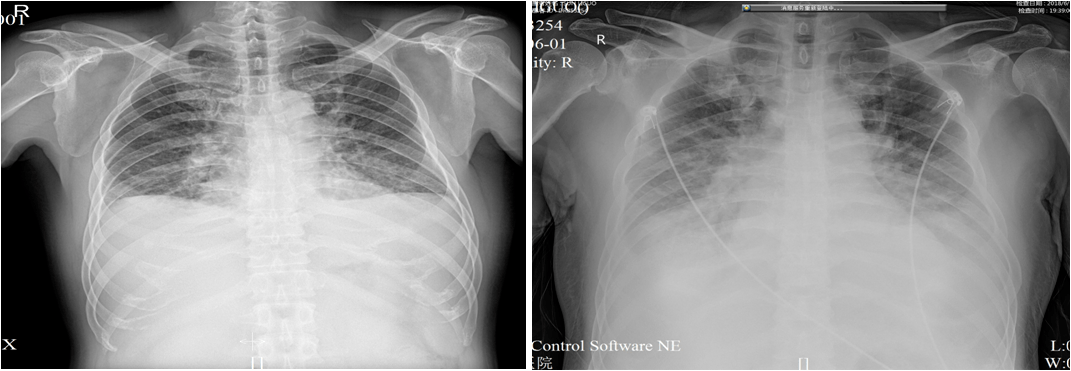

st 段抬高就是心梗?你对 st 段的理解可能错了

心电图示:v1-v5st抬高,q波形成,急性广泛前壁心肌梗死61 ctni3.